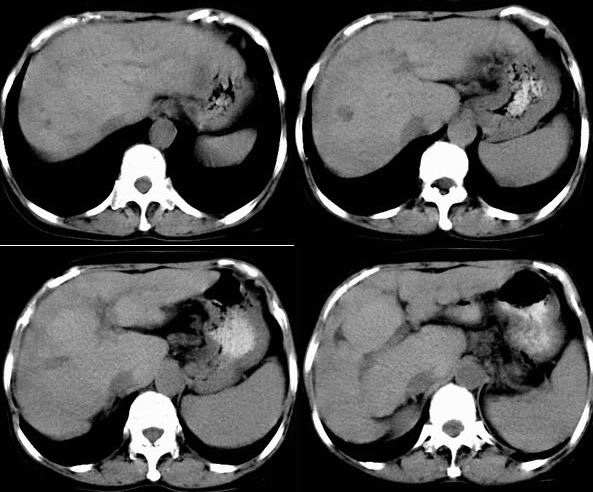

患者,女,53岁。恶心、上腹痛、下腹胀、消瘦2月余。曾有肝硬化、乙肝、胆囊炎病史。

b超发现肝右叶实质性占位,做ct检查。

静脉期

此病灶不具备典型小肝癌的强化方式,从动脉期及静脉期看病灶是呈逐渐强化。

结合病史及b超表现,考虑肝癌合并脂肪变性可能大。平扫病灶密度较一般常见肝癌密度偏低,增强动脉期强化不明显,但长期的肝炎及肝硬化病史,不能不考虑肝癌的可能性,合并脂肪变性,病灶强化的程度就会明显减低。建议必要时mri三期增强扫描。

考虑为肝硬化,脾大。没有足够证据有肝癌。要是有延迟扫描就比较好了。

动脉期无增强,静脉期可见部分增强,考虑肝内胆管细胞癌,